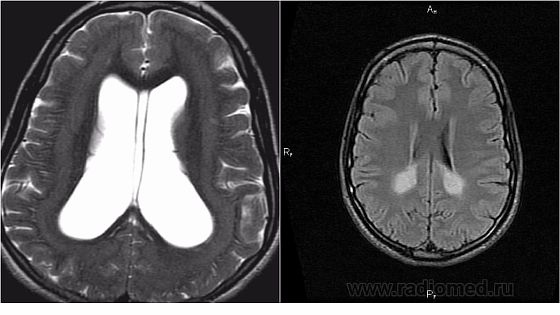

Заболевание бывает разных видов, но наиболее распространенное – это перивентрикулярная лейкомаляция, так как очаги повреждений белого вещества мозга находятся в его перивентрикулярной области. Размер данных очагов около 2 миллиметров. Находятся они в лобковых и теменных долях мозга с двух сторон и симметрично стенкам боковых желудочков.

В основном болезнь развивается в первые пару часов после рождения ребенка, однако под наблюдение следует находиться 10 дней. Недостаток поступления кислорода в мозг приводит к застою крови, образованию тромбов и отмиранию пораженных болезнью участков. Помимо этого может встречаться кровоизлияние в отмершие участки мозга или его желудочки.

Длительное кислородное голодание может привести к отмиранию нейронов головного мозга. Так у новорожденных развивается некроз. На том месте, где ранее были нейроны, начинают образовываться кистозные соединения разной величины. После двух недель развития заболевания нервные ткани головного мозга атрофируются.